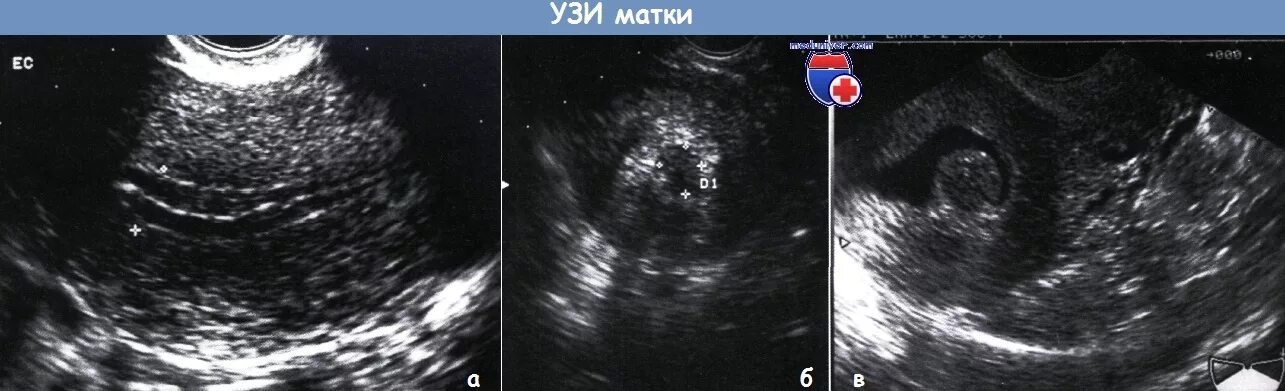

Пышное эндометрия